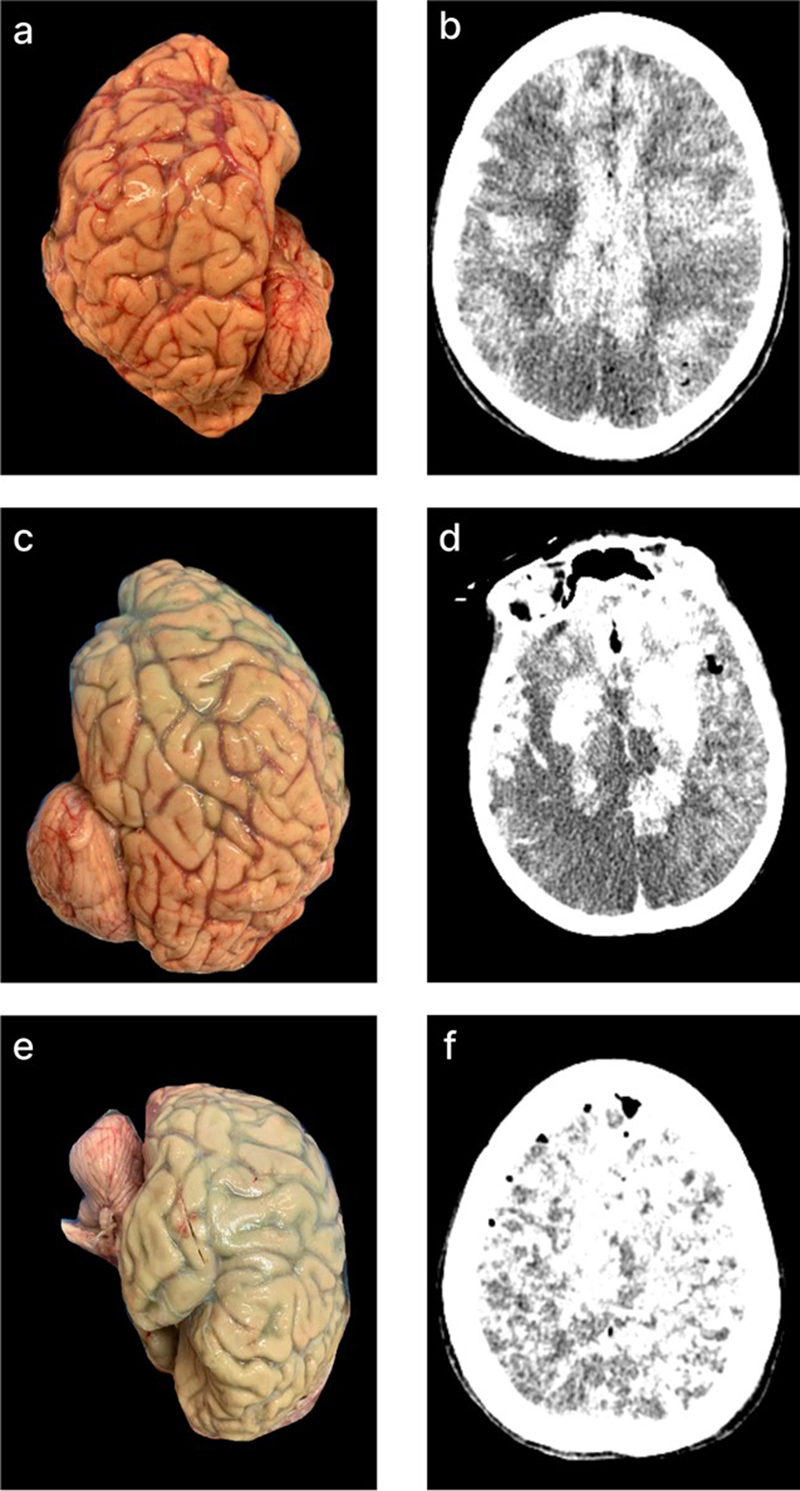

Correspondence between the quality metrics

Qualitatively, we found that in many cases, there was a spatial correlation between the perfusion profiles visualized via gross examination and those detected on CT scans (Figure 11). We also provide a representative example of perfusion correspondence across all three modalities: a brain from a 54-year-old donor with a PMI of 36.5 hours, which exhibited similar perfusion quality grades throughout the brain as measured by gross examination, CT imaging, and histology (Figure 12).

Figure 11.

Representative matched gross examination and CT images illustrating spatial correlations in perfusion quality across modalities. On CT images (b, d, f), following standard radiologic convention, the right side of the image corresponds to the left side of the brain. In one of these perfused brains, a clear anterior-to-posterior gradient of perfusion is observed, with relatively better perfusion in the anterior regions and relatively worse perfusion in the posterior regions; this gradient is visible in both gross examination images (c) and CT scans (d). Donor IDs: 205 (a, b), 207 (c, d), 185 (e, f).

Figure 12.

Representative gross examination, CT scan, and histology findings in a single brain. This brain was assessed a perfusion quality grade of 2 in all regions across all three modalities. Gross examination images: right lateral view (a), inferior view (b), left lateral view (c), and coronal CT images (d–g). H&E histology from the right frontal cortex (h, zoom in l), right temporal cortex (i, zoom in m), left temporal cortex (j, zoom in n), and left frontal cortex (k, zoom in o). Donor ID 107, PMI of 36.5 hours. Scale bars: 6 mm (h, i, j, k) and 200 μm (l, m, n, o).